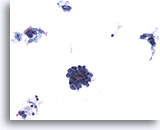

Figure 87

Bronchial wash

This cluster contains many abnormal cells. Their nuclear detail is seen at the periphery of the cluster. 20x

Bronchial wash

This cluster contains many abnormal cells. Their nuclear detail is seen at the periphery of the cluster. 20x

Figure 87

Bronchial wash

This cluster contains many abnormal cells. Their nuclear detail is seen at the periphery of the cluster.

20x

Bronchial wash

This cluster contains many abnormal cells. Their nuclear detail is seen at the periphery of the cluster.

20x